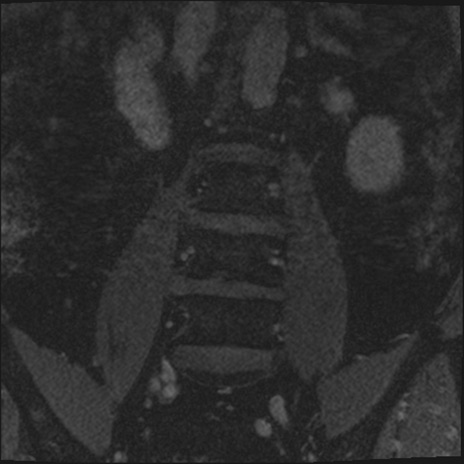

【整形】TIPS症例2 腰椎MRI 3D(冠状断像)

【症例】70歳代男性

【主訴】左下肢痛

【現病歴】2週間前くらいから腰痛、左下肢痛あり。左臀部から大腿、下腿外側のしびれが常時ある。歩行とともに同部位の痛みあり。

【身体所見】Lasegue70-/60+、Bragard-/±、PTR ±/±、ATR -/-、IP 5/5、TA 5/4、TS 5/5、EHL 右第1足趾なし/3、FHL 5/5、hypersthesia(-)、足背動脈触知良好

異常所見と診断は?